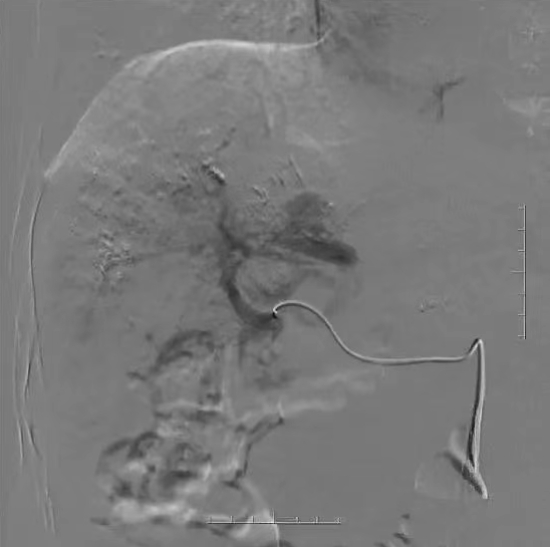

术前增强CT示肝内多发血管瘤

术中造影及栓塞